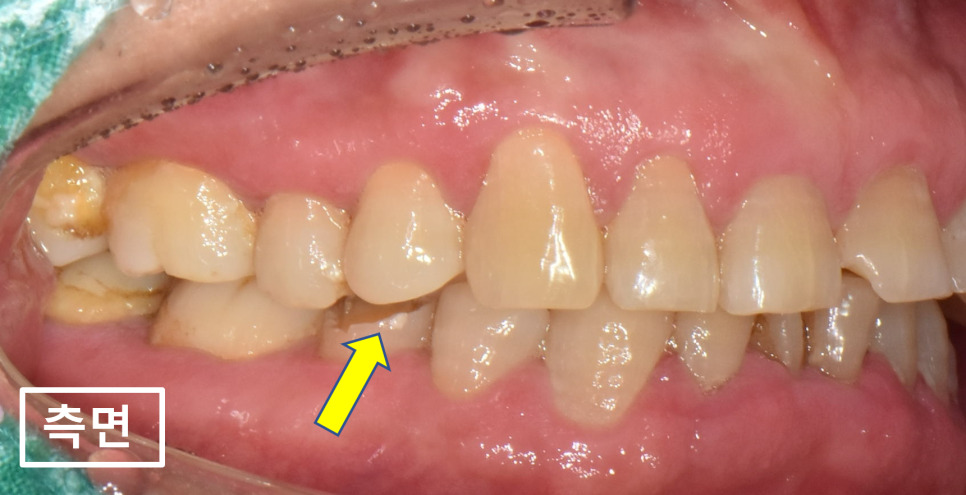

자, 앞니통증이 있는 치아는 뒤에서 살펴보기로하고

고혈압환자의 입안사진부터 쭉 살펴보겠습니다.

노랑색화살표를 보면 앞니가 깨져있습니다.

다른 앞니들의 마모도 상당한 편이네요.

24.02.01(초진) – 69y 김OO님

오른쪽, 왼쪽 측면 사진입니다.

노랑색화살표를 보시면 양쪽 작은어금니들이

전부 깨져있습니다.